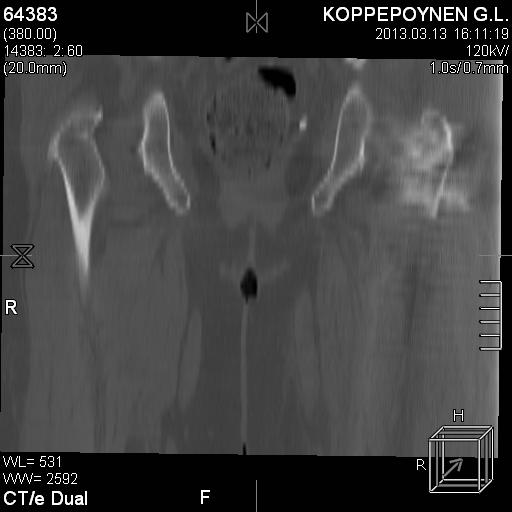

Делали КТ после операции.

Непонятно, на какой вопрос с помощью КТ хотели получить ответ? IMHO это было ненужное исследование, все проблемы были видны на обычном снимке. А что на второй проекции? Где аксиальная или профиль?

есть КТ после операции. у пациентки направление введения стержня совпадает с направлением большого вертела, однако большой вертел расколот на 2 отломка. Задний отломок лежит по оси, передний отломом "отошел" и создается впечатление неправильного введения стержня. Динамизации у пациентки не было... Привезут снимки после операции, скину